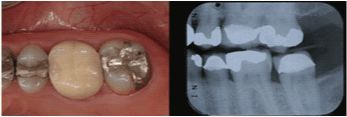

| Maxillary Left Second

Premolar |

12 |

74.4% |